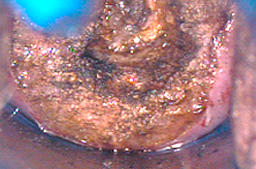

ECTROPION DE GRAN EXTENSION, tratado mediante fotovaporización con láser CO2

Cicatrización al mes del tratamiento y cicatrización al sexto mes del tratamiento